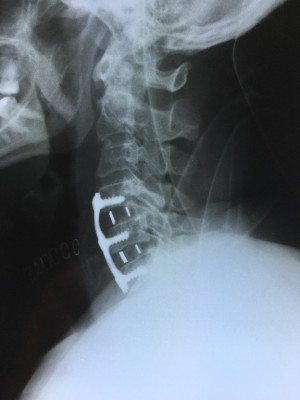

Cirugía de columna de mínima invasión

Envíado por Dr. Hugo Enrique Castro Cordero